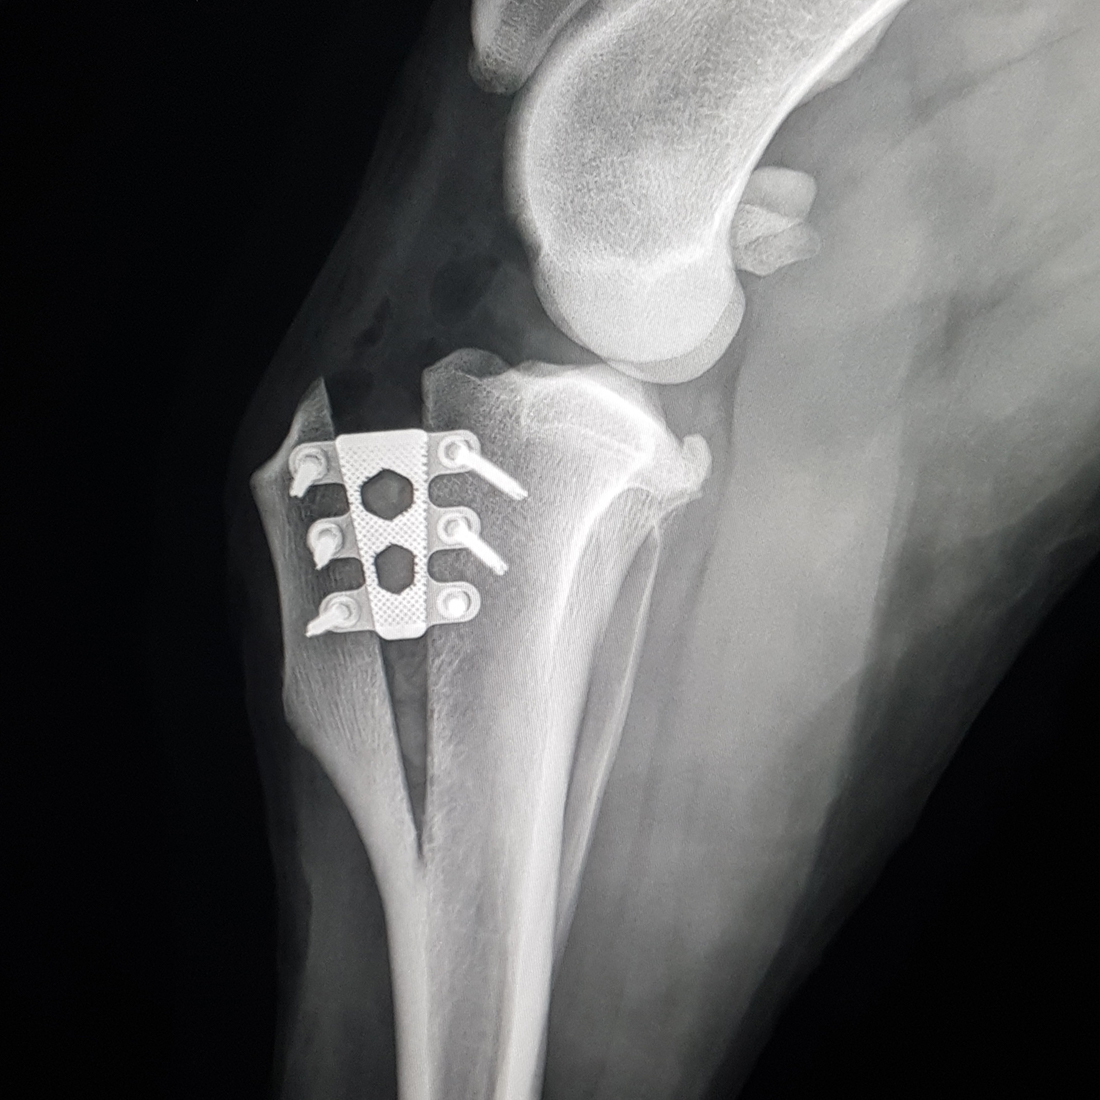

TTA RAPID ®

Now with 59 different cage sizes, TTA RAPID® is the most flexible surgical technique designed to repair a cruciate ligament injury. It allows for shorter surgery times, which means lower risk of infection and less costs.

TTA RAPID® & RAPID Patella Luxation